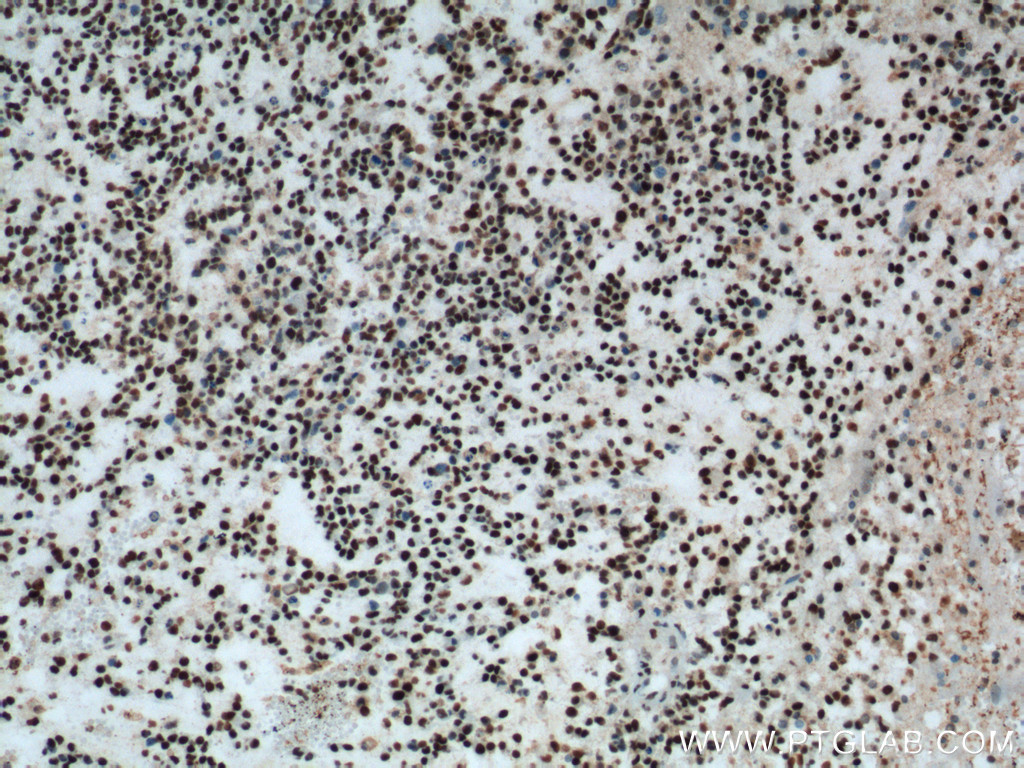

| Figure 1. Immunohistochemical staining of paraffin-embedded human gliomas tissue slide using 60160-1-Ig (FUS/TLS monoclonal antibody) at a dilution of 1:1000 (under 10x lens). A heat mediated antigen retrieval step was performed with Tris-EDTA buffer (pH9). |